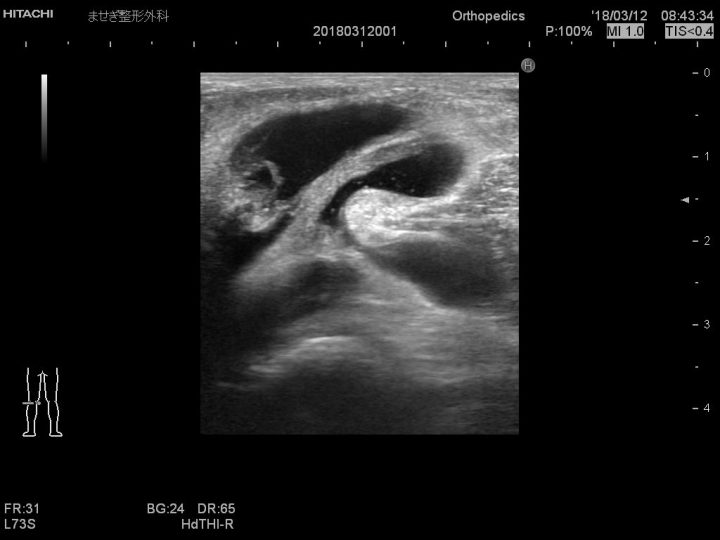

医師は通常、膝の身体検査を行った後にベーカー嚢胞を診断できます。

医師は通常、特に基礎疾患がある場合、患者との問診と膝の身体検査を行った後にベーカー嚢胞を診断できます。

場合によっては、動脈瘤や腫瘍などの他の疾患を除外するために追加の診断検査が指示されることがあります。

次の非侵襲的テストが実行される場合があります。

• 超音波スキャン

• CTスキャン

• MRI スキャン